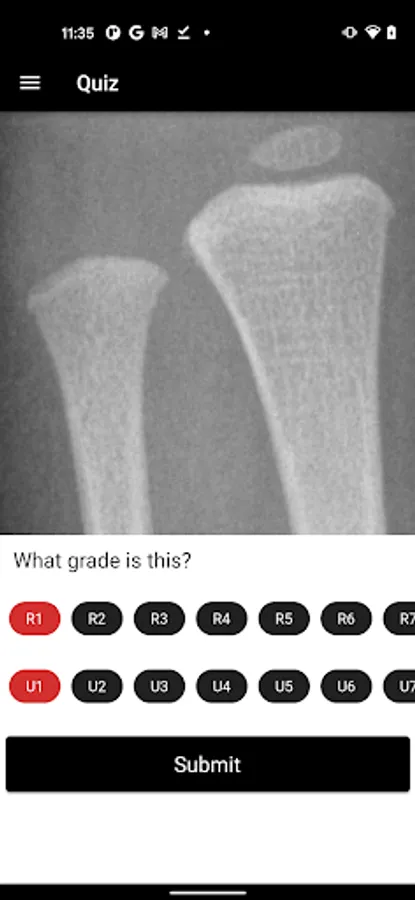

2. Distal radius and ulna features on x-rays for grading

3. DRU grading quiz